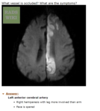

loss of central vision leading to a relative afferent pupillary defect

imaging shows optic nerve inflammation but upon examination retina appears normal. loss of central vision.